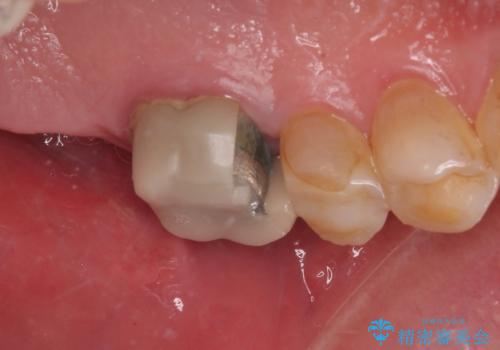

欠損した奥歯 インプラントによる補綴治療

しかしながら、レントゲンやCT画像から、手前の破損したクラウンの根尖部に大きな病変が認められ、インプラント埋入部にまで病変が及んでいることから、まずは手前の根管治療を行い、病変の正体を確認した後にインプラント埋入を行うこととしました。

口があまり開かず、インプラントの埋入角度がやや斜めとなりましたが、機能的には全く問題なく治療を終えることができました。